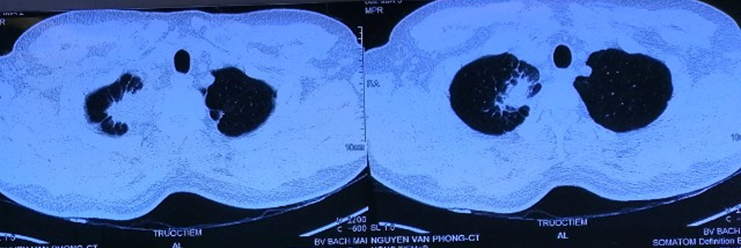

Chụp cắt lớp vi tính lồng ngực sau điều trị: Hình ảnh khối u thùy trên phổi phải kích thước 3×2 cm

So sánh trước và sau điều trị:

Trước điều trị: Hình ảnh khối u thùy trên phổi phải kích thước 5x6cm

Sau điều trị 6 tháng: Hình ảnh khối u thùy trên phổi phải kích thước 3×2 cm

Sau điều trị 9 tháng:

Hình ảnh khối u thùy trên phổi phải kích thước 1×2 cm.